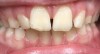

Dental impactions may occur for several reasons. A common occurrence is insufficient arch length leading to crowding. Another potential reason is early loss of primary teeth without proper space maintenance, allowing the permanent dentition to drift mesially and block out the primary tooth's successor. Maxillary canines are the most commonly impacted teeth besides third molars. These teeth have the longest path of eruption, are one of the last teeth to erupt into the mouth, easily become blocked out due to crowding or trauma history, and have a genetic component to being palatally impacted.5,6 Early signs of canine impaction may be severe crowding and the permanent lateral incisor crowns flaring distally. The crown of the impacted canine, in essence, is applying pressure to the roots of the lateral incisors in these instances (Figure 3 and Figure 4).

Fig 3. Impacted canine, dentofacial signs.

Figure 3